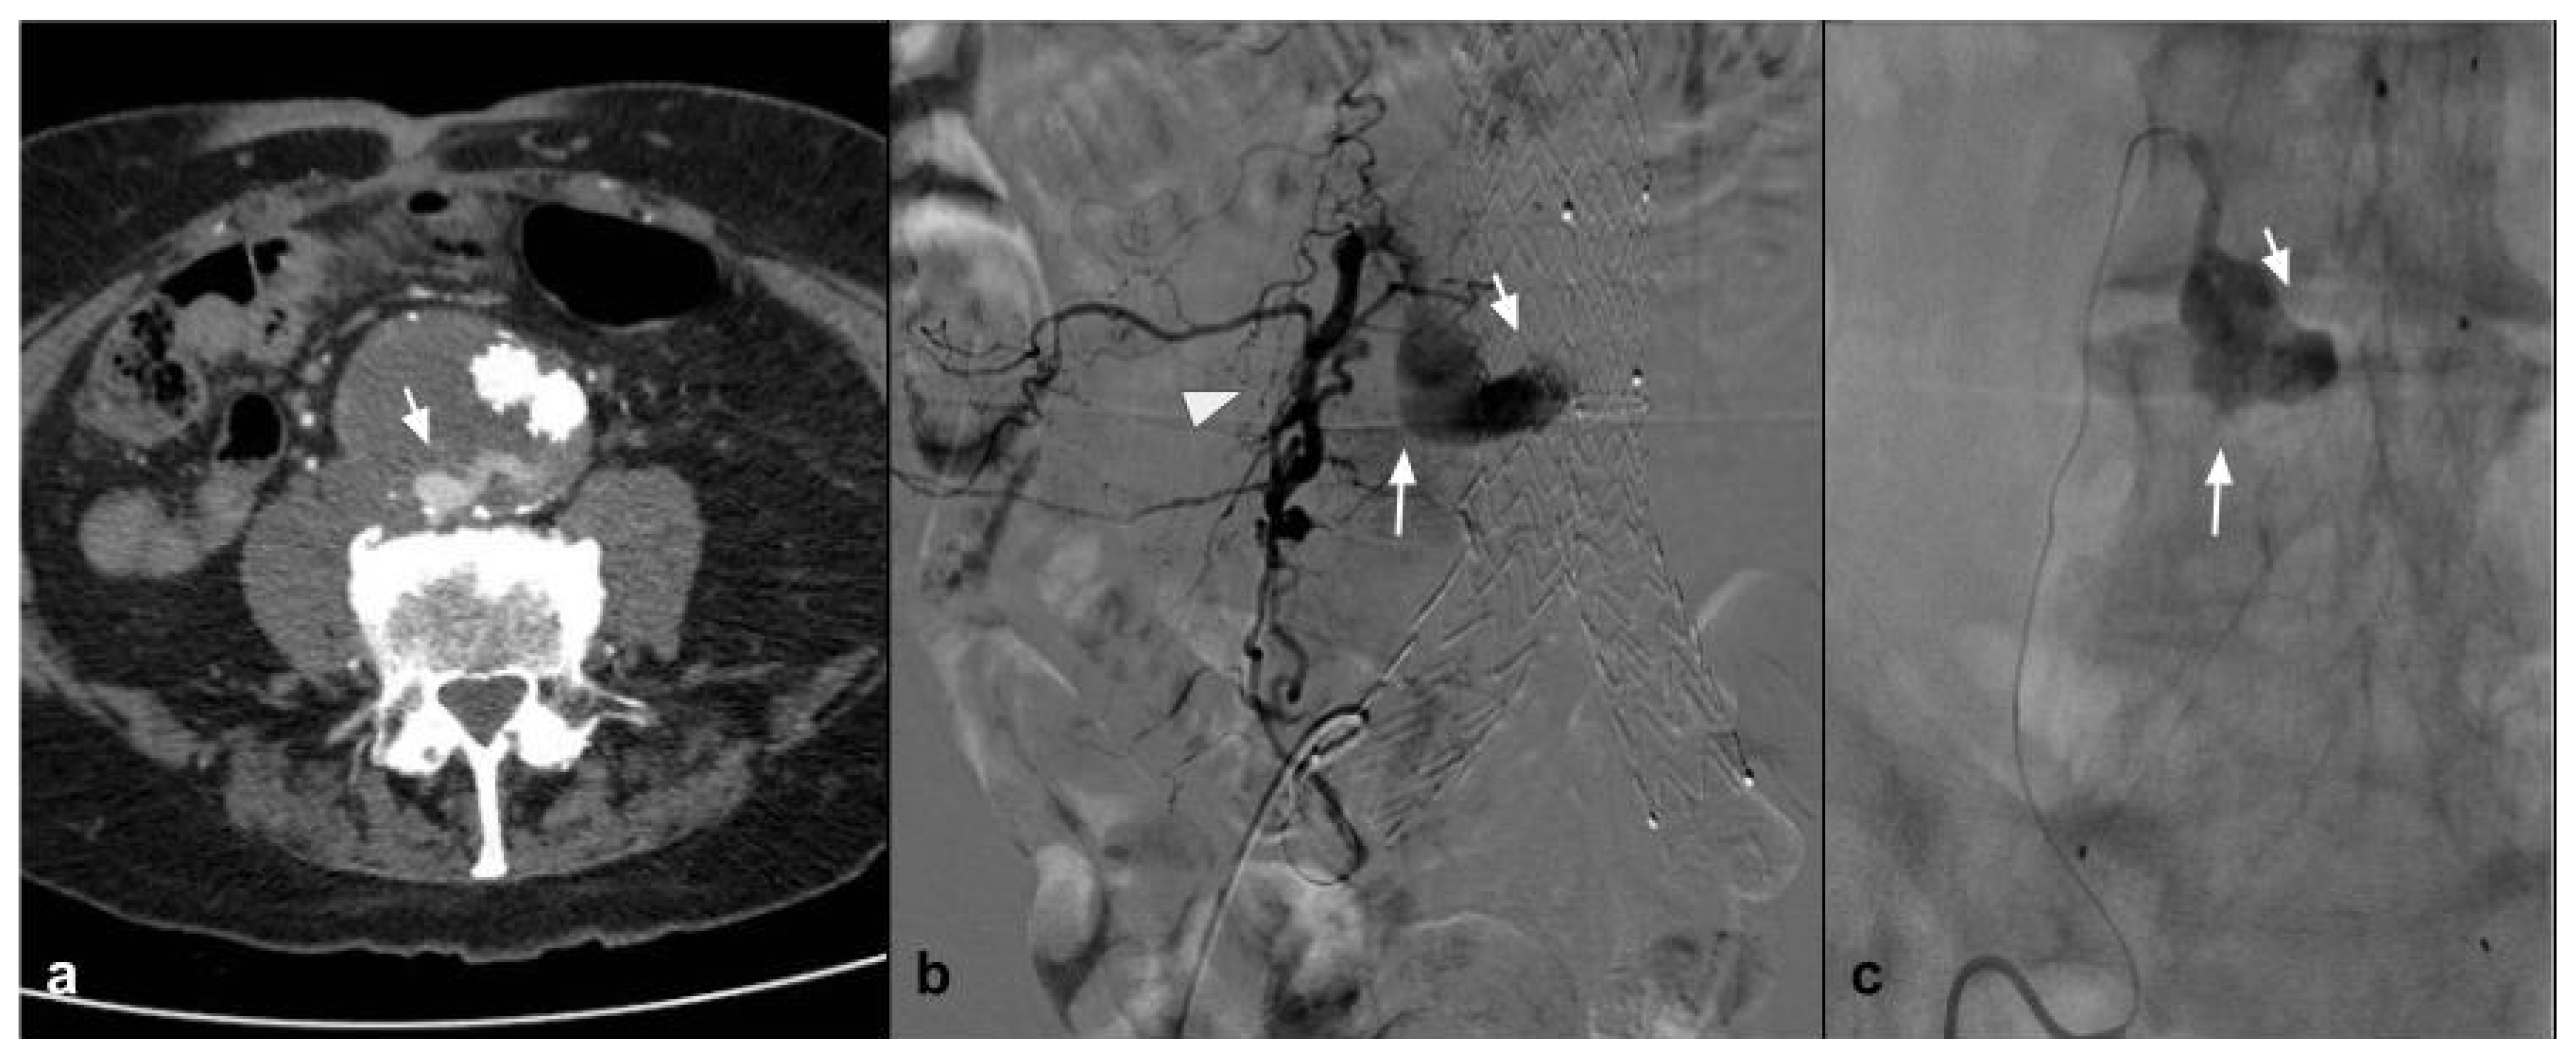

This new generation of embolizing agents has further advantages, excellent embolizing capacity of the treated vessel, and is able to reach vessels with a diameter of 80 microns (Figure 2).

Figure 2.

(a) Coronal CTA MIP demonstrates hypertrophic bronchial artery with tortuous course originating at 9:00 from the convexity of the aortic arch (white arrows); (b) DSA performed with Simmons 1 catheter at the level of the ostium of the bronchial artery confirms the presence of the hypertrophic vessel (black arrow) with a small tributary branch of the right upper lobe (arrow head); (c) single-shot fluoroscopy after embolization shows the presence of the microcatheter at the level of the proximal portion of the bronchial artery, with a Squid 12 cast completely occupying the main trunk (white arrows); (d) post-procedure DSA control demonstrates complete exclusion of the treated vessel (asterisk) with patency of the small branch for the right pulmonary upper lobe (white arrow).